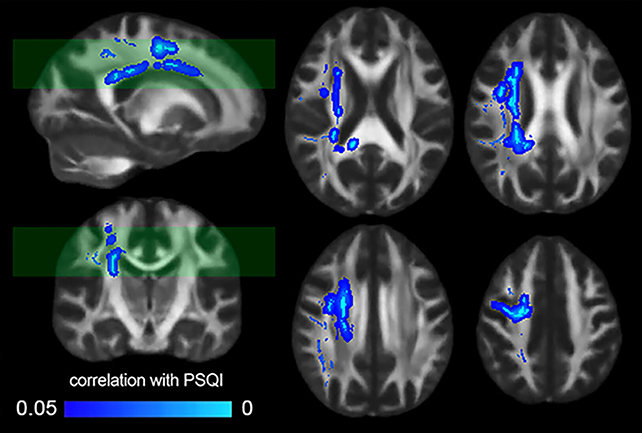

Cercetătorii au analizat scanările MRI a 185 de voluntari sănătoși, confirmând rezultatele studiilor anterioare care au constatat că integritatea structurilor materiei albe din creier a scăzut odată cu o scădere auto-raportată a calității obiceiurilor de somn.